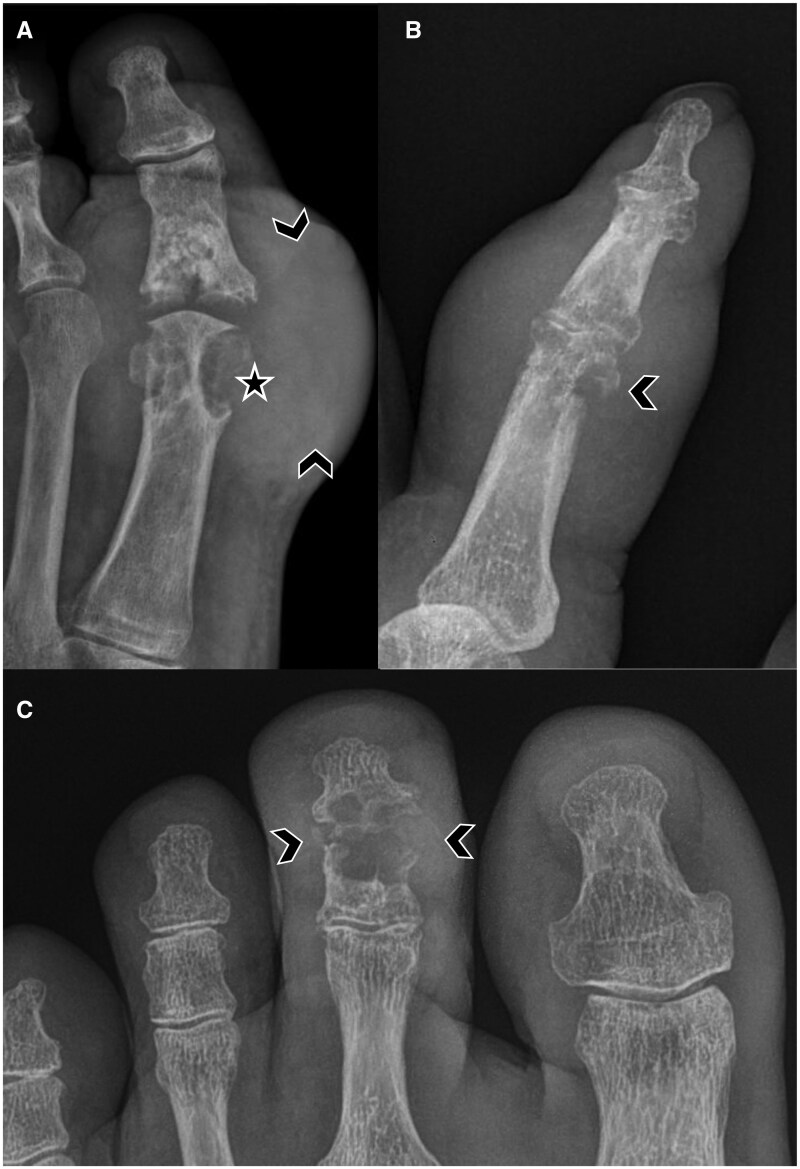

痛风是一种常见的全身性疾病,由尿酸钠(MSU)晶体沉积在关节和关节周围结构,导致反复发作的炎症。当晶体吸吸不可行、临床诊断不确定时,影像学对确定诊断有重要作用。每种成像方式都有其独特的作用。x光片可以显示痛风后期的特征性侵蚀和痛风。超声在痛风的诊断和评估中起着重要作用。双能计算机断层扫描(DECT)可以精确地显示MSU沉积物,并可以确定疾病负担。MRI可以评估非特异性炎症和结构改变。超声和DECT都被强调为诊断算法的一部分,随着最近的进展和证据,成像的作用正在扩大。这篇综述提供了一个以成像为中心的每一种模式的概述及其在痛风中的发展意义。

Gout is a common systemic disease defined by deposition of monosodium urate (MSU) crystals in articular and peri-articular structures, leading to recurrent bouts of inflammation. Imaging plays an important role in establishing the diagnosis when crystal aspiration is not feasible and the clinical diagnosis is uncertain. Each imaging modality has a unique role. Radiographs can demonstrate characteristic erosions and tophi in later stages of gout. Ultrasound has a major role in the diagnosis and assessment of gout. Dual-energy computed tomography (DECT) enables precise visualization of MSU deposits and can determine disease burden. MRI can assess for non-specific inflammatory and structural changes. Both ultrasound and DECT are emphasized as part of diagnostic algorithms and the role of imaging is expanding with more recent advancements and evidence. This review provides an imaging-centric overview of each modality and its evolving significance in gout.